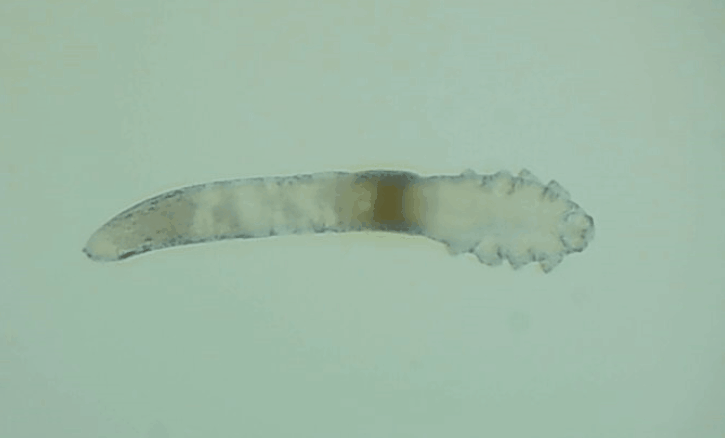

是的, 眼睛也會(huì)有蟲(chóng)子,那就是蠕形螨。眼睛發(fā)紅、干癢、疲勞、睫毛脫落,這些都是因?yàn)樗?/div>

其實(shí)蠕形螨主要活動(dòng)在毛囊和皮脂腺中,以皮膚碎屑和腺體分泌物作為食物來(lái)源,而睫毛根部的瞼板腺是排泄油脂的重要部位,因此眼睫毛和瞼板腺也是螨蟲(chóng)的主要活動(dòng)場(chǎng)所。

一般來(lái)說(shuō),15天內(nèi),一只蠕形螨會(huì)在你眼睛里產(chǎn)下50只蟲(chóng)卵。如果不及時(shí)除螨,它們會(huì)迅速繁殖,從而導(dǎo)致睫毛脫落、亂生、眼睛紅癢,甚至引發(fā)眼部炎癥。如果影響到角膜,就會(huì)造成視力下降甚至失明。

在廈門眼科中心檢查后發(fā)現(xiàn),在她的眼睛上竟然有大量的螨蟲(chóng),僅是檢查用的2、3根睫毛上就有8只,除螨蟲(chóng)外,她的眼睛還出現(xiàn)了瞼緣炎以及干眼癥。